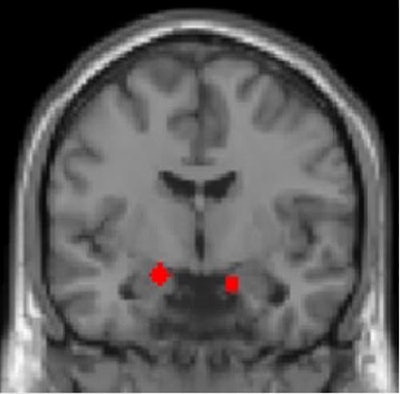

The researchers used fMRI to find that both smaller amygdala volume and responses to face stimuli in the amygdala independently predicted the severity of PTSD symptoms. What's more, the group also discovered differences in other brain regions involved in response to threat learning, such as the striatum, hippocampus, and dorsal anterior cingulate cortex.